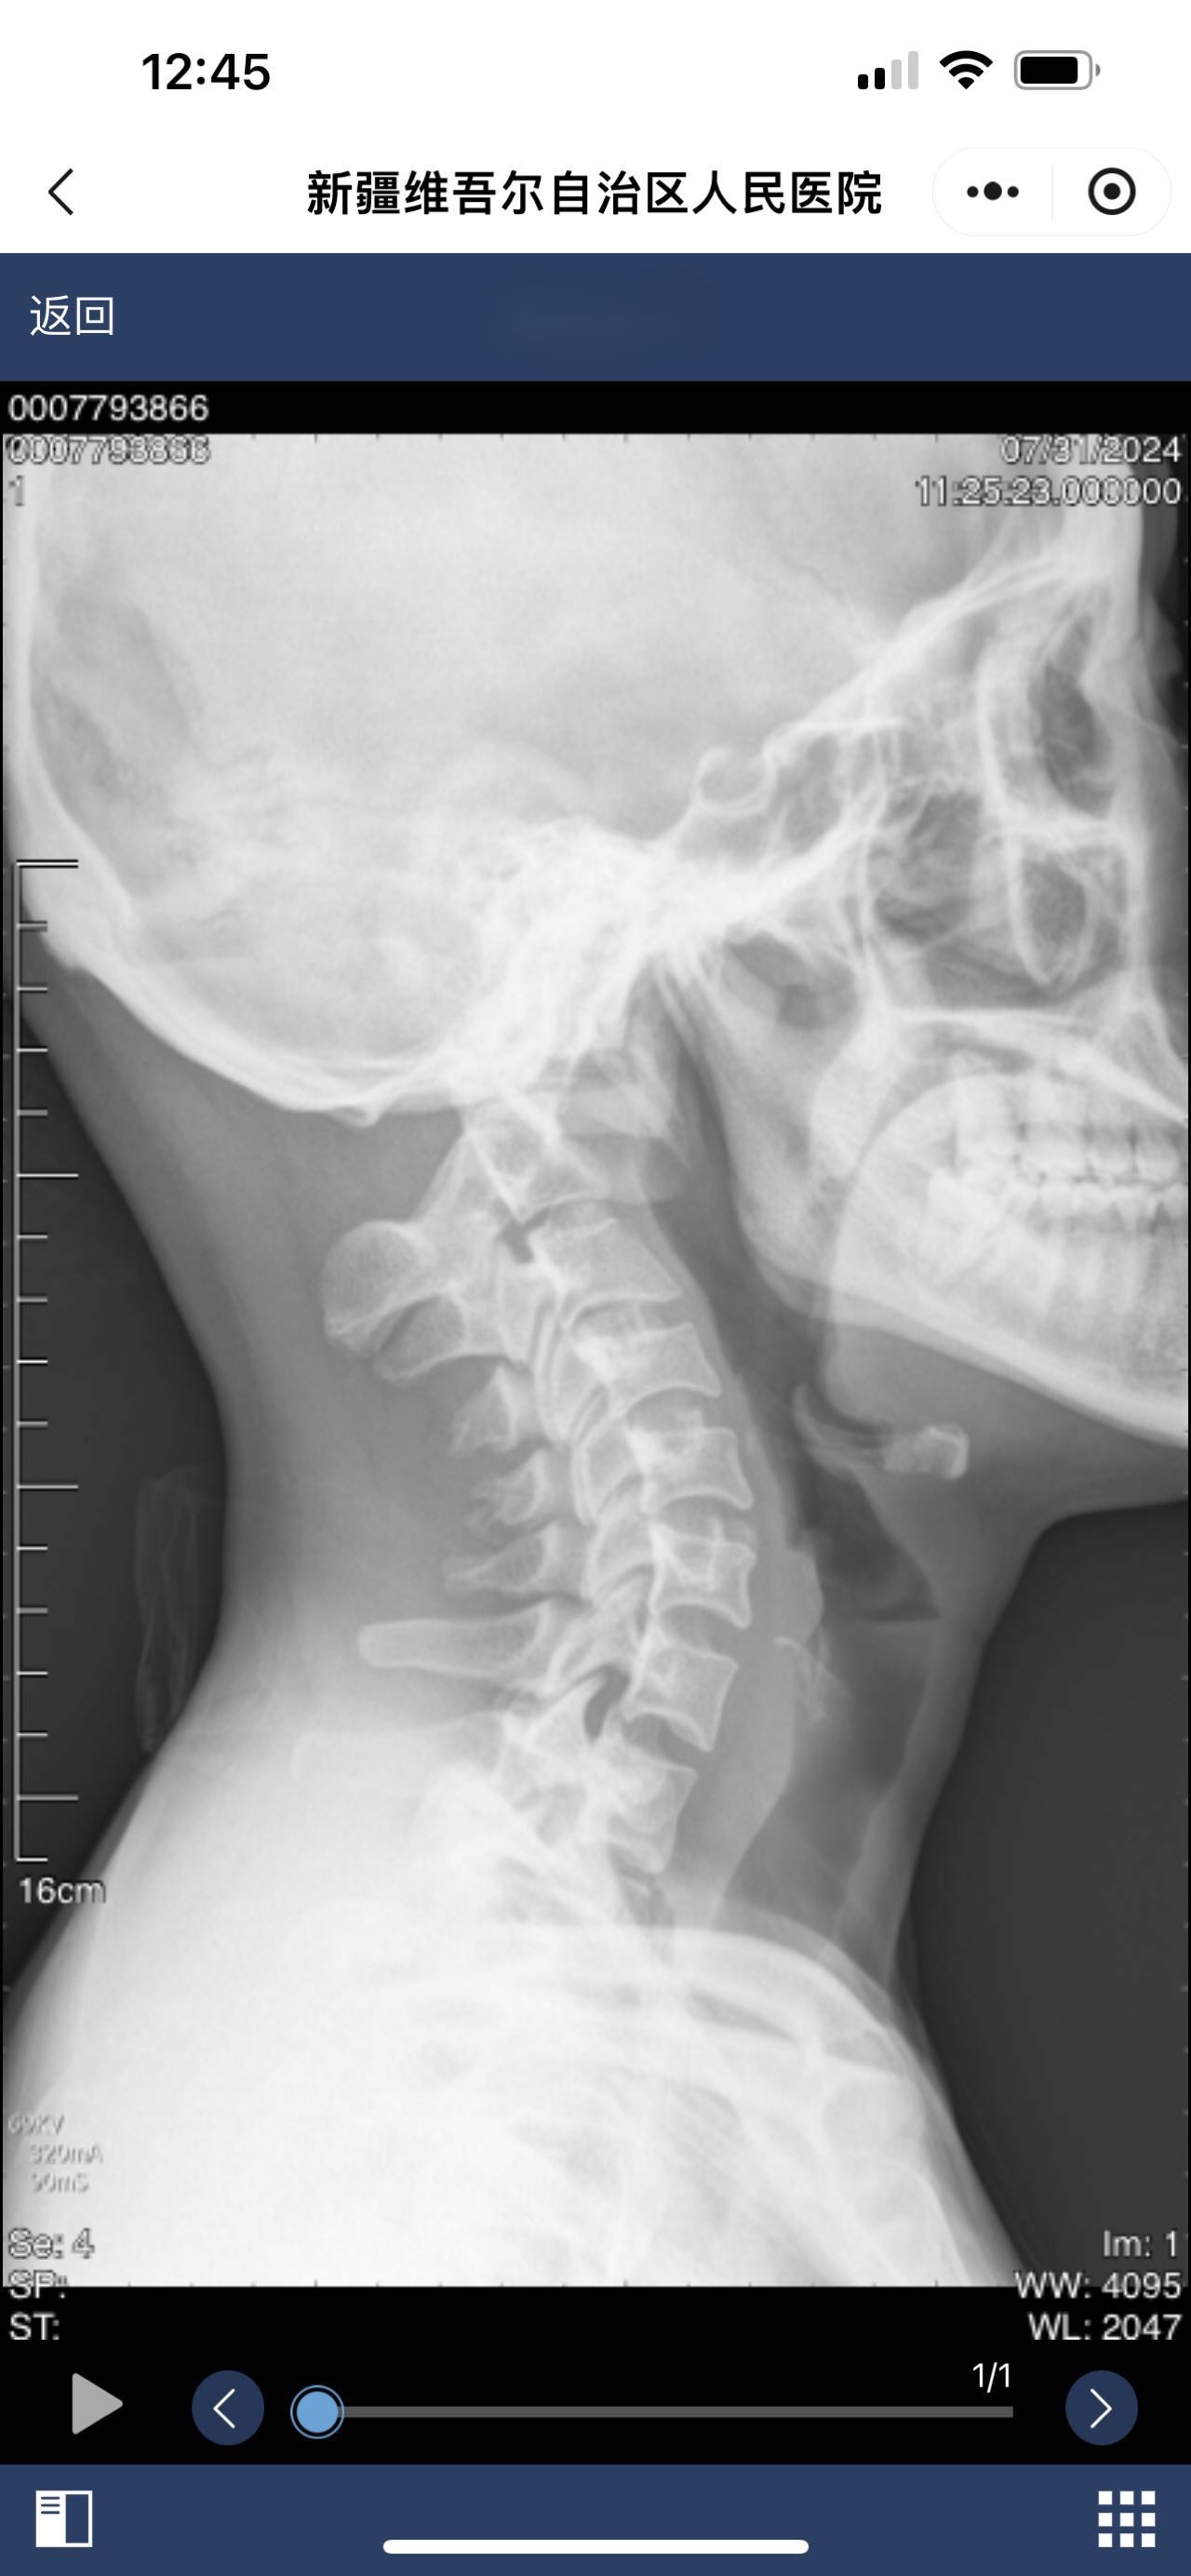

• 诊断日期:2024.07.31

• 诊断:颅底凹陷

• 影像: